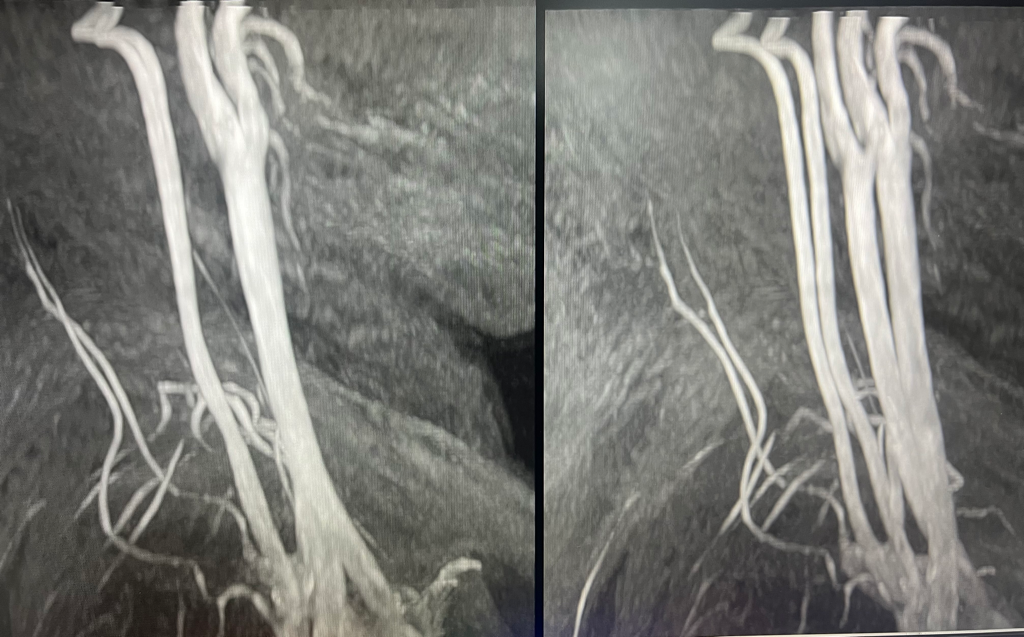

저의 목혈관사진인데 이상이 있는건가요 의사는 없다고 하시던데..

목 혈관이 큰 이상은 없다고 하는데도 뒷목이 늘 불편하고 어지럽고 소화도 잘 안되요. 그리고 열이 많아서 열도 더 자주 올라와요. 답변 부탁드려요

목의 혈관 사진은 모든 각도를 돌아보며 관찰해야 하지만 보이는 사진으로는 깨끗하고 혈류도 좋아보입니다. 증상의 원인을 다른 곳에서 찾아보셔야 하겠습니다.

• 올리신 사진 한 컷만 놓고 정확하게 어떻다 이야기 하기는 어렵습니다만, 사진의 소견에서는 특별히 협착이 보이거나 하는 부분이 따로 있어 보이지 않습니다.